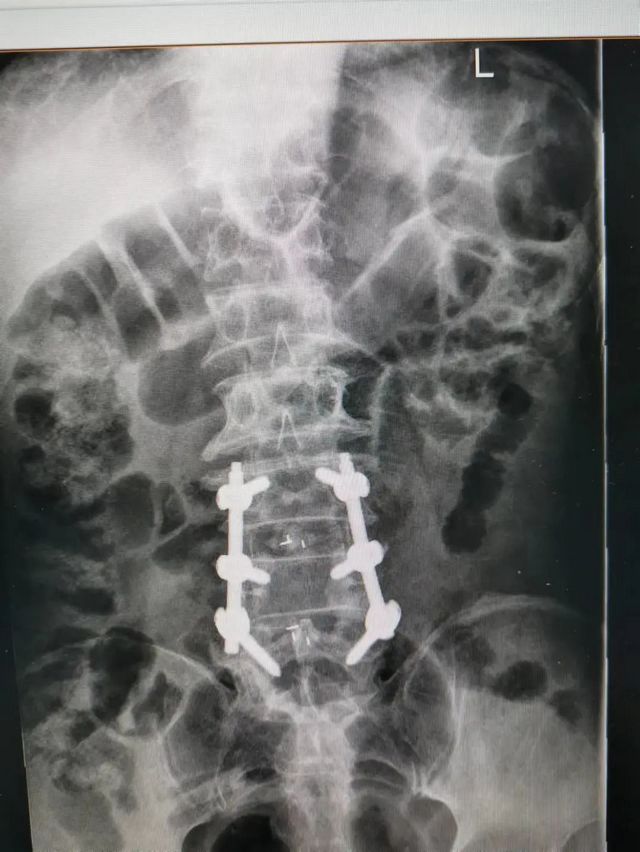

杨先生腰椎管狭窄症拍片

原来,杨先生无明显诱因的出现颈肩部、腰部疼痛,在当地医院住院治疗后症状稍缓解,随后疼痛症状又加重,并反复发作。近日,杨先生状况已是下地行走困难,还伴四肢疼痛、麻木、无力等,为求进一步治疗,杨先生来到泸州市中医医院就诊。经检查,杨先生是患了脊髓性颈椎病加腰椎管狭窄症。